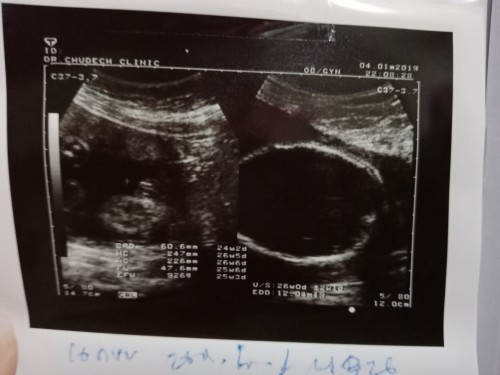

26week กำหนดคลอด เดือน ธ.ค จ้า

กำหนดคลอดเดือน ธ.ค ตอนนี้26วีคแล้วจ้า ได้ลูกสาว น้ำหนักตัวเล็กในท้องแม่ๆกี่กรัมแล้วคะ บ้านนี้926กรัมแล้วคะ น้ำหนักแม่ขึ้นมา2โลจ้า